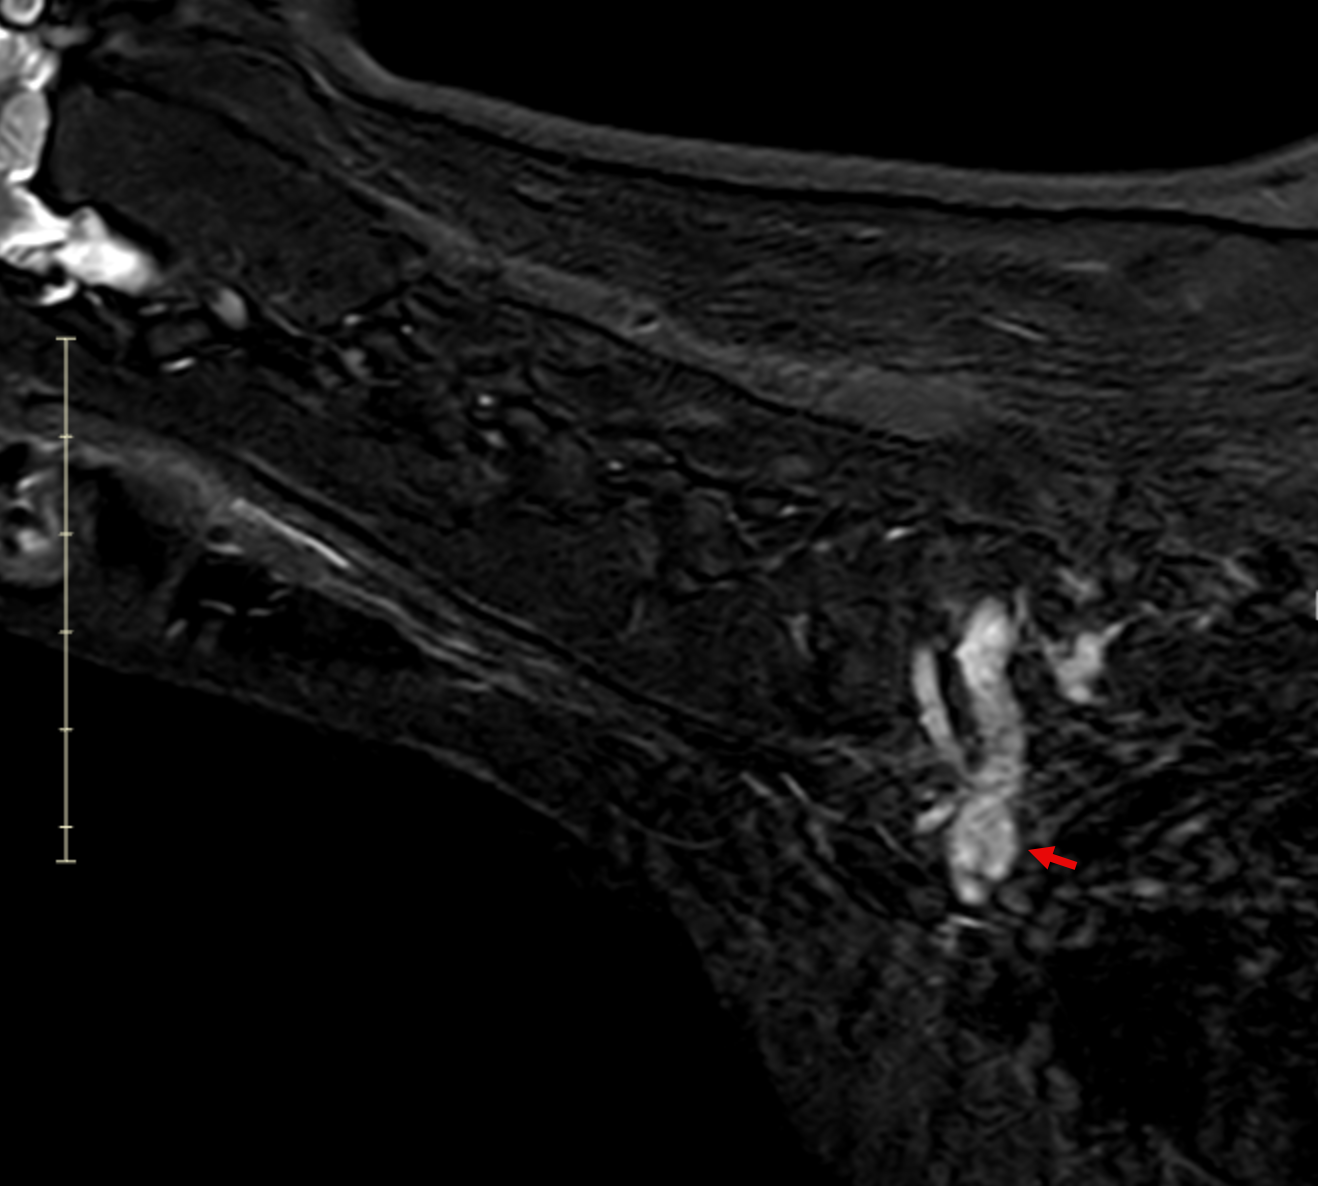

Dorsal post-contrast MRI of a dog cervical spine showing enhancing lesion at C7 to T1 nerve roots extending into the brachial plexus

Image 5. Dorsal post-contrast MRI of the cervical spine and thoracic inlet demonstrating a contrast-enhancing lesion associated with the left-sided C7–T1 nerve roots extending into the brachial plexus.

Sagittal post-contrast MRI of a dog showing tubular mass along cervical nerve roots with spinal cord compression

Image 6. Sagittal post-contrast MRI demonstrating a tubular, contrast-enhancing mass extending along the left cervical nerve roots into the brachial plexus, with associated spinal cord compression.

Transverse MRI of a dog showing enlarged C7 to T1 nerve roots with contrast enhancement and spinal cord displacement

Image 7. Transverse post-contrast MRI showing asymmetric enlargement and contrast enhancement of the left C7–T1 nerve roots with associated spinal cord displacement, consistent with a nerve sheath tumor.

MRI revealed a clinically significant and previously undetected diagnosis (Images 5-7):

Primary Diagnosis: Nerve Sheath Tumor

• Contrast-enhancing mass involving the left C7, C8, and T1 nerve roots

• Extension from the spinal canal through the intervertebral foramen into the axilla and brachial plexus

• Severe spinal cord compression with displacement

• Expansion of the C7–T1 neural foramen

• Associated neurogenic muscle atrophy of the left forelimb (triceps)